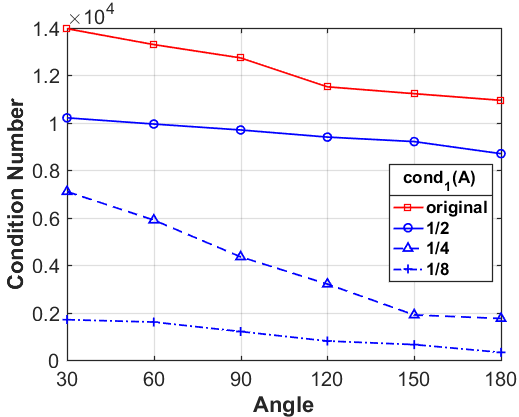

Next, we numerically compare the condition numbers of the system matrices for both the low-resolution and original reconstruction problems by 1-norm, 2-norm and -norm, respectively. As shown in Fig. 8, we can observe that the condition numbers of the low-resolution reconstruction problem are much smaller than the original reconstruction problems for different scanning angles, which are consistent with our theoretical analysis. In fact, larger condition numbers allow for undesired solutions, which also numerically satisfy the forward model (1). More importantly, the constraint in our model (2) can help to find better solution from the null space, which has already been perfectly demonstrated by our numerical experiments.

What is more, as shown in Table III, IV and V, the smaller the down-sampling rate, the better the reconstruction result. Since the quality of the image prior decreases as the resolution decreases for the limited-angle reconstruction problems, there is a trade-off between the resolution and the quality. Thus, we track the relationship between the resolution of the low-resolution image priors and the performance of our LRIP-net. As shown in Fig. 9, the best reconstruction results are obtained using the low-resolution image prior with down-sampling rate . Although the smaller the condition number of the system matrix, the better the numerical stability of the solution, it does not mean that the better the performance of our LRIP-net.